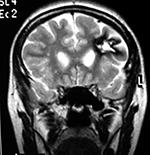

EJEMPLO DE CASO CLÍNICO (8)

Paciente femenino de 29 años de edad con historial de cefalea crónica que presenta súbitamente disdiadococinesia y dismetría izquierda.

El estudio de RMN presenta una lesión bien circunscrita en hemisferio cerebeloso izquierdo con periferia de predominio hiperintenso en T1 y T2, y centro hipointenso, edema perilesional mínimo, así como una imagen de un vaso venoso alimentador que recorre hacia el ángulo pontocerebeloso izquierdo.

Se realizó una craniectomía suboccipital paramedial derecha, así como un abordaje transcortical en el hemisferio cerebeloso izquierdo llegando a la región perilesional de aspecto amarillento, posteriormente se observa una lesión oscuro-verdoso de contenido hemático antiguo, retirando la cápsula y su contenido en la totalidad.

La evolución clínica de la paciente fue satisfactoria solo preservando la dismetría como secuela.

El resultado histopatológico fue consistente en angioma cavernoso.

El estudio de control de RMN se observa la brecha quirúrgica y ausencia de lesión (figs. 1, 2 y 3).

Figura 1:

Lesión cerebelosa izquierda ponderaciones en T1 y T2, la flecha señala vaso nutricio hacia el ángulo pontocerebeloso izquierdo, se puede observar el centro de intensidad heterogénea con contenido quístico multiloculado y edema perilesional leve.

Figura 2:

Cortes axiales en ponderación T1, cambios postquirúrgicos.